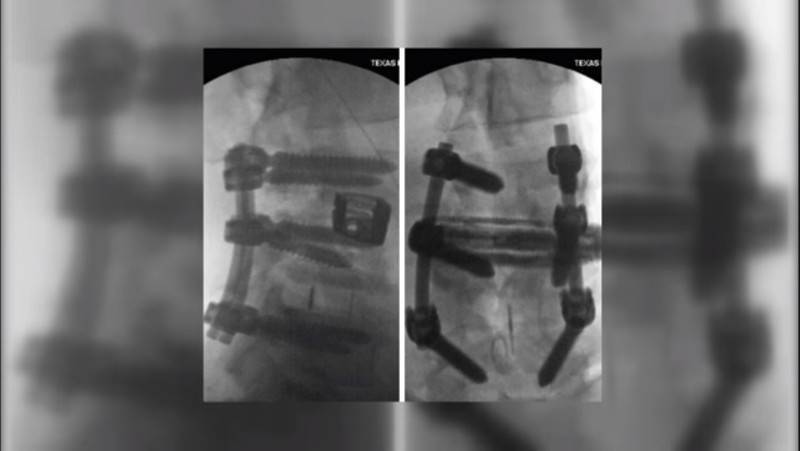

На заметку! Позвоночник Ронни Коулмена удерживают подпорки, которые часто ломаются. В итоге приходится снова вскрывать грудную клетку и спину, чтобы их восстановить.

В августе 2017 Ронни делился тем, что ему предстоит, по

крайней мере, еще одна очень серьезная операция. Те самые 6 болтов, которые ему

в свое время вкрутили в позвоночник – теперь нужно было удалить.

Фото. Болты Ронни Колемана, которые необходимо удалить